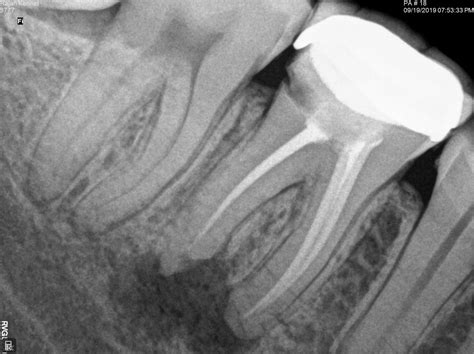

A root canal treatment is a specialized procedure designed to save a tooth that has been severely damaged by decay, disease, or trauma. During the process, the infected or inflamed pulp inside the tooth is carefully removed. The inside of the tooth is then cleaned, disinfected, shaped, and filled with a rubber-like material called gutta-percha. Finally, a crown or filling is placed to seal the tooth and restore its full function.

• RCT Radiograph

• RCT Molar